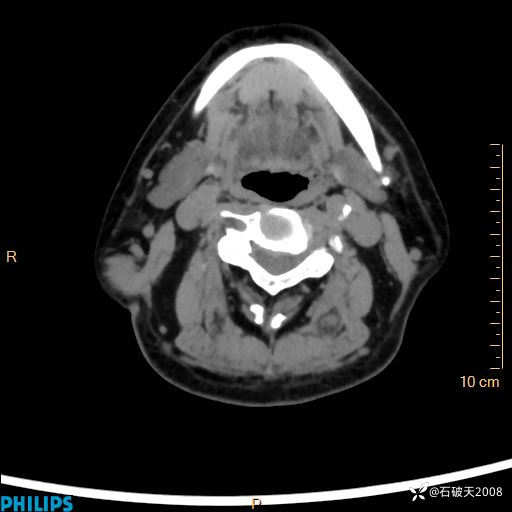

MIP